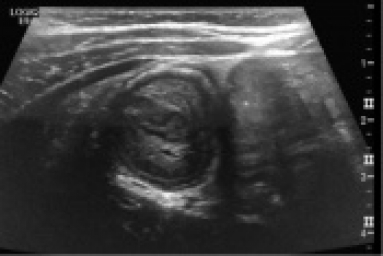

2 year-old male with no PMHx is brought to the ED for intermittent abdominal pain for the past two days. Mom notes that the child will crouch down into a ball when he has pain, which only lasts for a few minutes at a time. He has decreased solid food intake but no vomiting or diarrhea and is otherwise well. Vitals and physical exam are unremarkable. The ultrasound is shown below…what’s the diagnosis?

Answer:  Intussusception

• Imaging may includes plain xrays demonstrating signs of bowel obstruction, but ultrasound should be considered as well. Ultrasound demonstrates the “target sign” demonstrated below